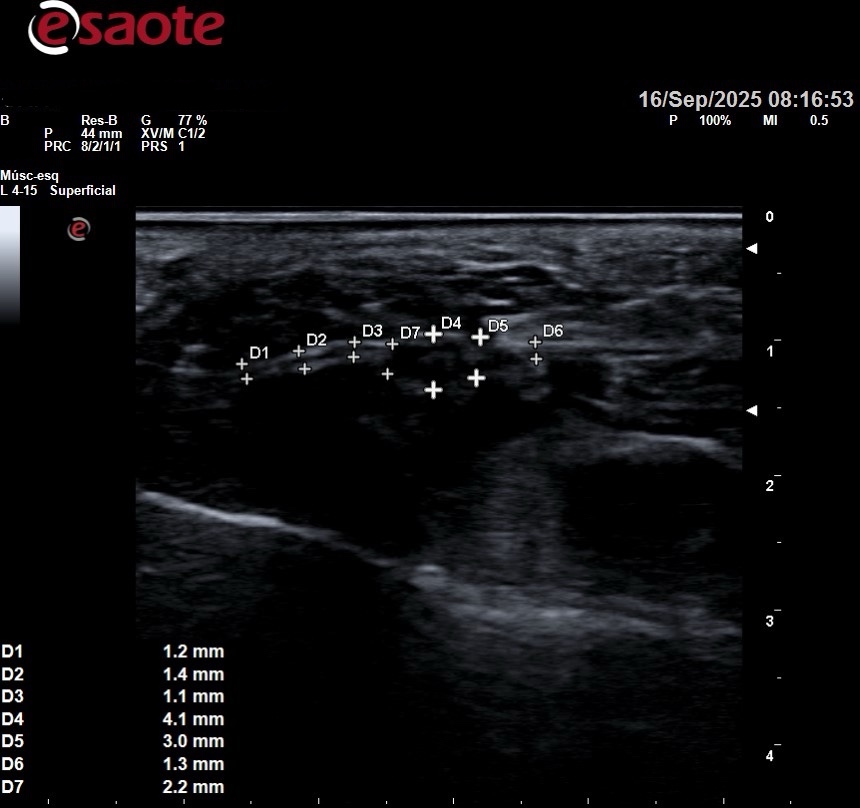

2. Aplicación de la radiofrecuencia

Con anestesia local, se introduce una aguja guiada hacia el nervio afectado para aplicar la energía térmica controlada.